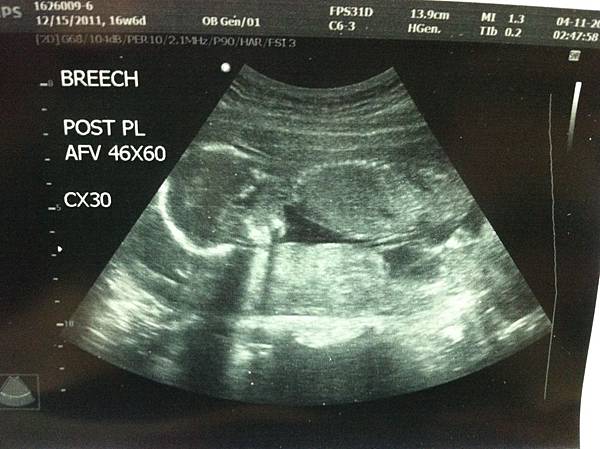

小寶的17週我們轉到了榮總來做產檢,

因為計畫要在榮總生產,

所以希望一切詳細的檢查都可以在這裡進行,